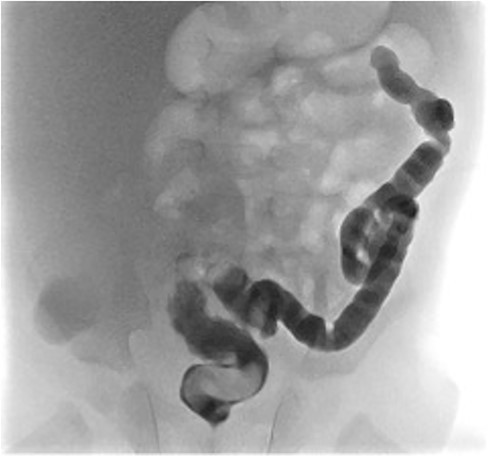

He presented at 6 weeks of age with circulatory shock requiring inotropic support and a short history of sudden abdominal distension and non bilious vomiting. He had been having regular episodes of SVT, all self limiting. Laparotomy demonstrated malrotation and a 540°midgut volvulus with extensive bowel necrosis. A fulcrum of ileum was densely adherent to the descending colon. Following intestinal resection he was left with 40 cm of small bowel from the duodenojejunal flexure, 2 cm of distal ileum and an intact colon. Following recovery from this acute episode he was managed for intestinal failure. A contrast enema was performed 10 days later in advance of stoma closure to examine the area of descending colon to which the ileum had been adherent at laparotomy. This demonstrated failure of passage of contrast proximal to the mid descending colon consistent with acquired colonic atresia (Fig. 1). Due to ongoing high stoma output and inability to progress enteral feeds, the infant proceeded to laparotomy, closure of jejunostomy, resection of colonic atresia, and anastomosis at 3 months of age. Macroscopic evidence of the atresia was encountered (Fig. 2). Histology reported a narrow calibre colon to either side of the atresia with fibrotic submucosa, focal fibrovascular proliferation, and clusters of giant cells. He subsequently achieved enteral autonomy.

Contrast enema showing failure of passage of contrast beyond descending colon.